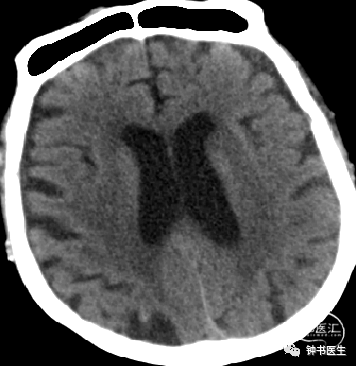

2012-11-8 CT

左颞部脑梗加重,出血渗出点增多。继续加强镇静镇痛治疗。

2012-11-10 CT

病情趋稳定,转出监护室治疗。